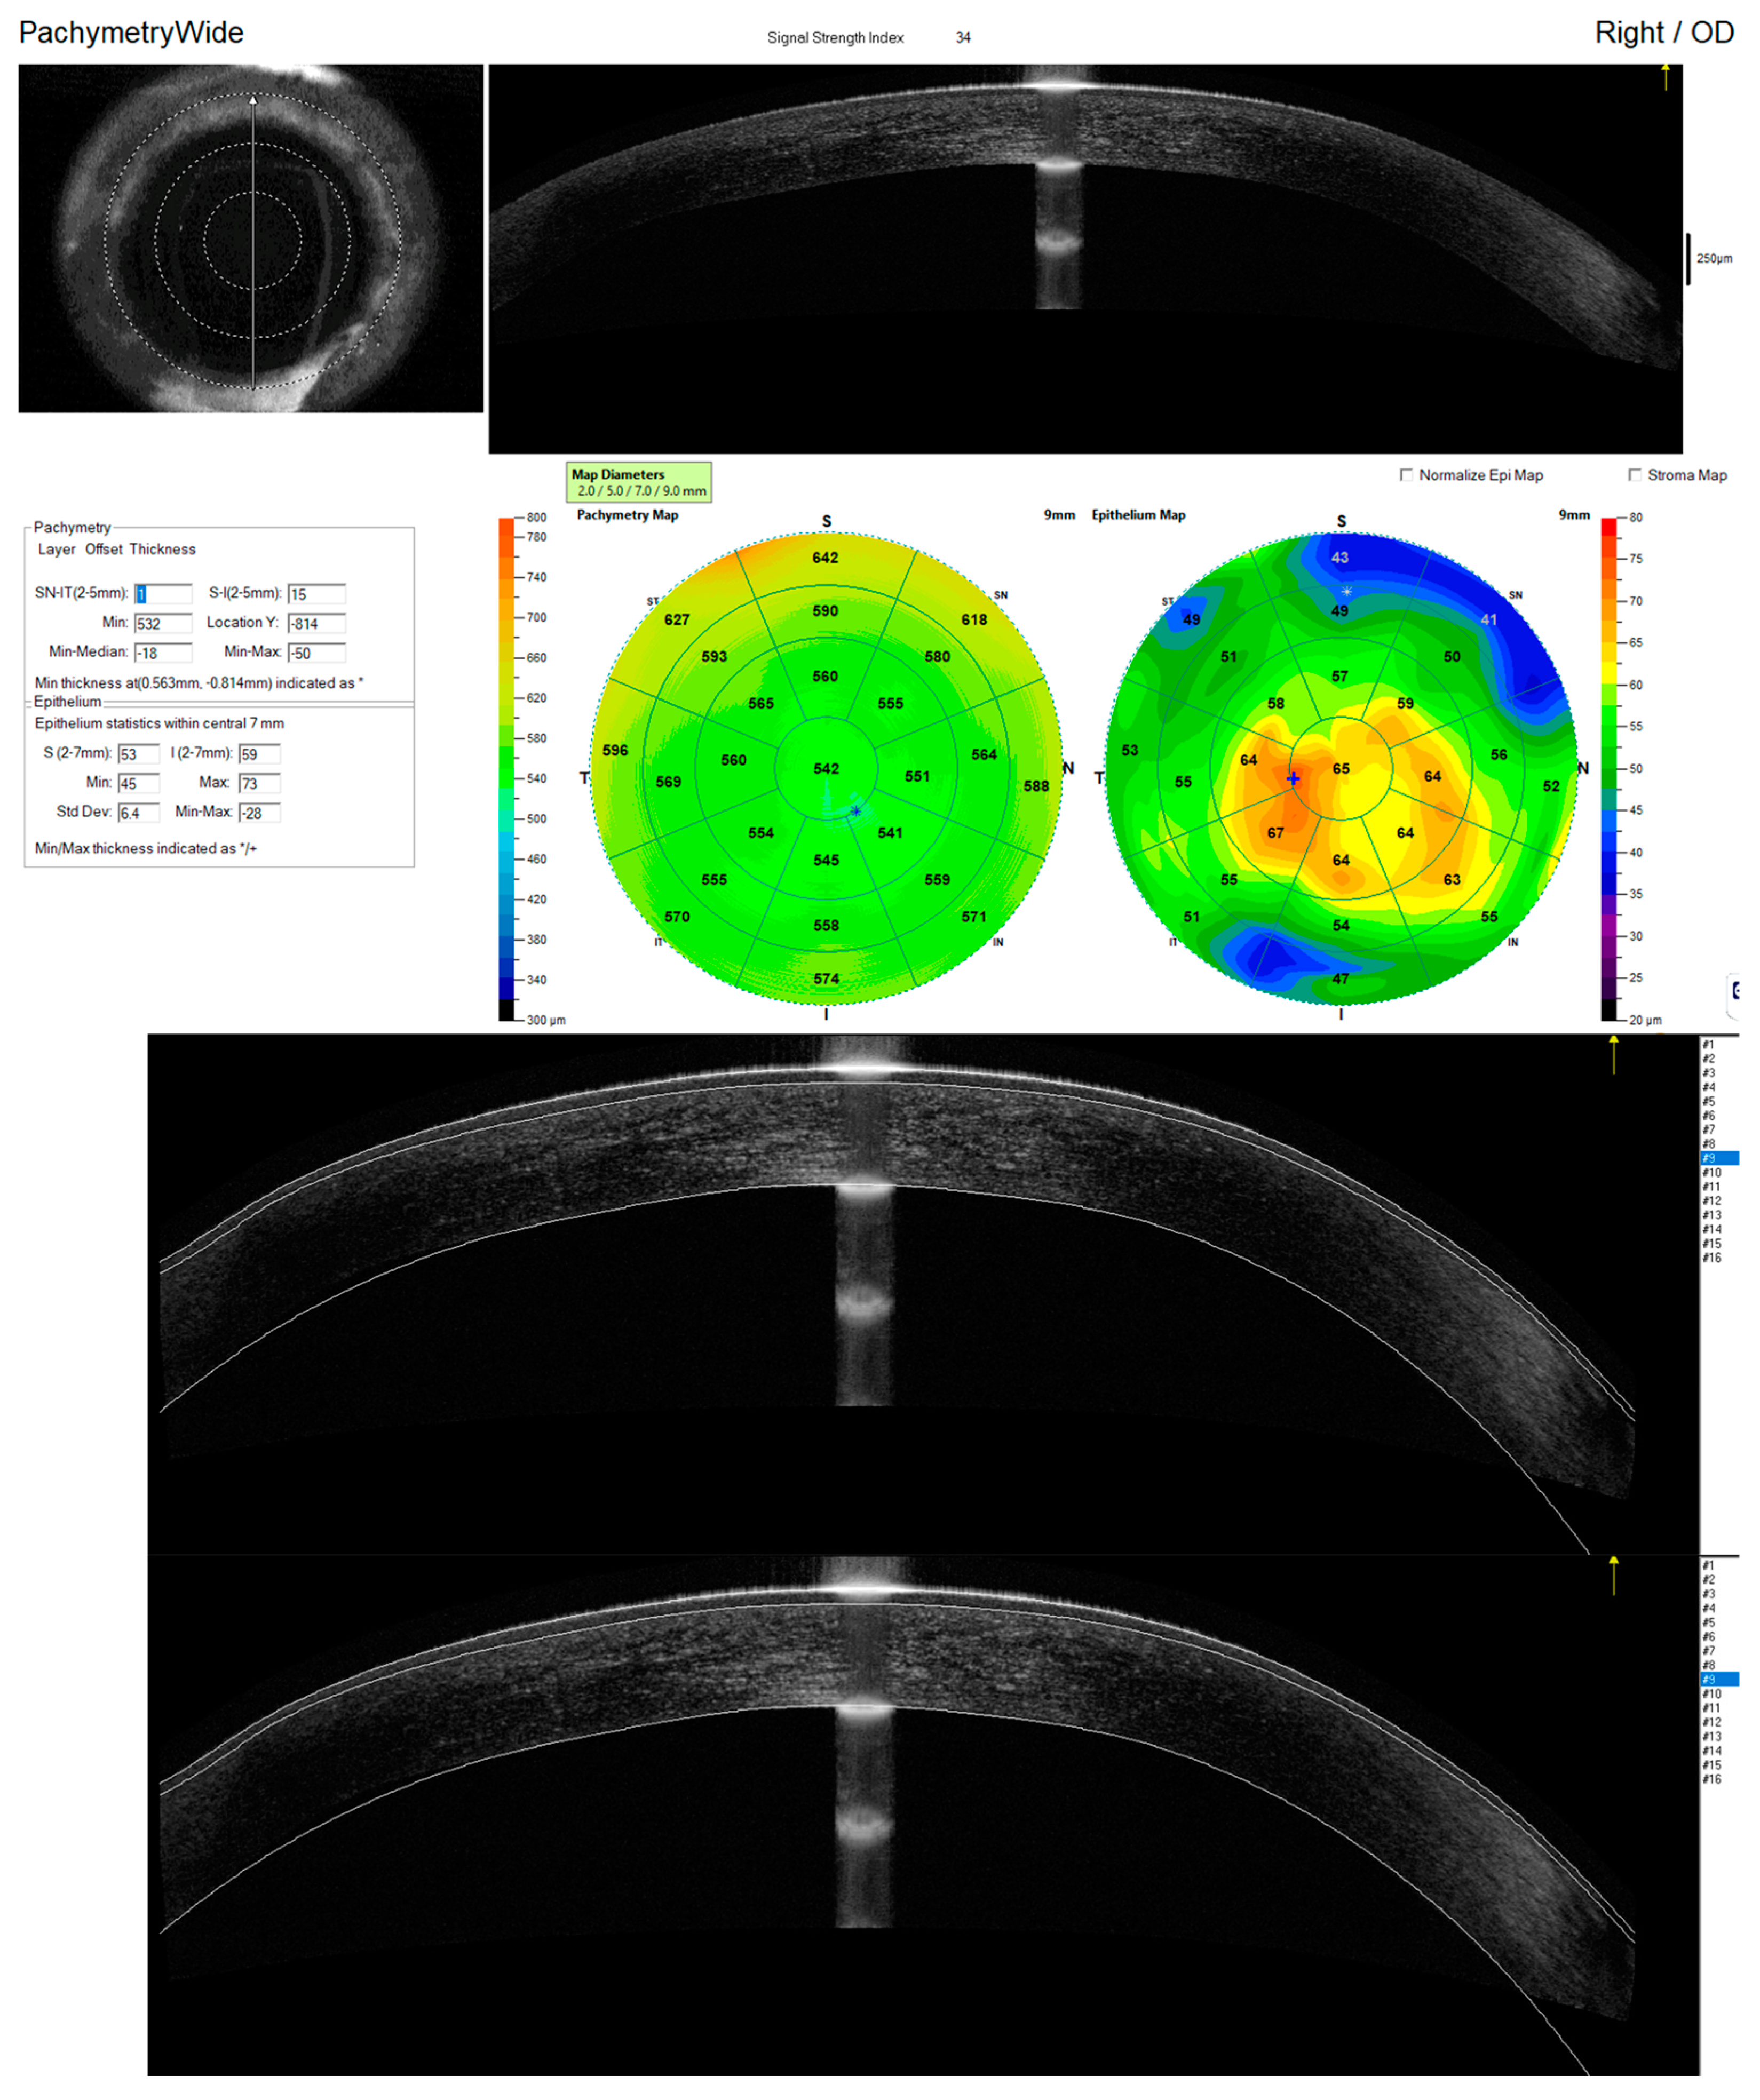

2. Materials and Methods

2.1. Study Procedures

2.2. Quality Assessment and Segmentation Correction

3. Results